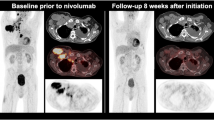

89Zr (t1/2, 78.41 h) is also an ideal radioisotope for immuno-PET [21–23]. However, 89Zr has also poor imaging characteristics because of low spatial resolution and image quality. Jin Su Kim’s group in KIRAMS, Korea, reported that the spatial resolution of 89Zr was approximately 9 % lower than that of 18F was using the Siemens Biograph Truepoint TrueV scanner (4.5 and 4.1 mm for 89Zr and 18F, respectively) [24]. The predicted spatial resolution of 124I was 5.5 mm on the Siemens Biograph Truepoint TrueV scanner [24]. The value of the β+ range was 1.23, 0.62, and 1.23 mm for 89Zr, 18F, and 124I, respectively. The low spatial resolutions of 89Zr and 124I were due to their long β+ ranges. The degradation of the spatial resolution was also observed with animal dedicated PET scanners. According to the report by Disselhorst’s group, the spatial resolution of 89Zr was degraded by 10 % compared with that of 18F on the Siemens Inveon PET scanner (1.99 and 1.81 mm for 89Zr and 18F, respectively) [25]. The β+ branching ratio of 89Zr was 23 %, which is lower than that of 18F, but similar to that of 124I. Furthermore, the low β+ branching ratio of 89Zr degraded the image quality compared with that of 18F [24]. Figure 1 shows the transaxial images of the National Electrical Manufacturers Association (NEMA) IEC phantom for the comparison of image quality between 89Zr and 18F. In addition, 89Zr emitted 909 keV of γ photons, which falls outside the energy window of clinical PET scanners, but the associated higher energy is still likely to cause Compton scattering. Furthermore, there was the possibility that the scattered photons would be included within the energy window, and produce some degree of noise [24]. Another problem associated with the 909-keV energy of γ photons was the radiation hazard, which was crucial for internal dosimetry and required the necessary provision of radiation protection for both patients and workers. Although there were limitations such as poor spatial resolution and image quality of the immuno-PET when 89Zr or 124I was used, they were a suitable match for the t1/2 of the mAb and, therefore, could provide a tool for monitoring the targeting of mAb to tumors.

Transaxial images of NEMA IEC phantom using (a) 89Zr images and (b) 18F. Images were reconstructed using FBP. This figure is reprinted from Lee et al. [24]